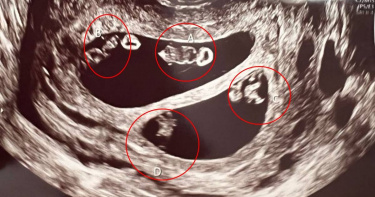

四胞胎不稀奇 她竟懷了「兩對雙胞胎」快嚇暈:機率僅7千萬分之1

這機率比中樂透還低!世界之大,無奇不有,有女懷過三胞胎、四胞胎,這已不足為奇,美國一名孕婦到婦產科產檢時,醫生一照超音波上,赫然發現該名孕媽咪的子宮,居然懷了「兩對」同卵雙胞胎,由於這在醫學上的機率只有7000萬分之1,這名媽咪一口氣懷了一對男孩與一對女孩,讓她快嚇暈。根據《每日郵報》報導,住在美國麻州的35歲女子內斯(Ashley Ness)與男友一直未能懷孕成功,後來好不容易有喜了,她到醫院進行例行產檢時,卻從懷孕喜悅變成快嚇到暈倒。原來醫生在幫他照超音波時,發現內斯不但懷了不只一個小孩,而且懷的竟是「兩對雙胞胎」,不是四胞胎。內斯說,當時醫生幫她照超音波時,第一時間非常困惑,還在超音波的螢幕上,自己標了A跟B清點腹中胎兒人數。當內斯找醫師確定,詢問「我要生雙胞胎了嗎?」但醫師就一臉慎重的說要暫時離開,要去確認一下狀況,後來經過醫生檢查,確認內斯懷的不是四胞胎,而是一對男孩與一對女孩的「兩對雙胞胎」。內斯回憶,她當時聽到這個消息後,簡直快要暈倒了,醫生還告訴她,這個機率僅7千萬分之1,不過內斯選擇既來之則安之,但她還在思考該怎麼告訴男友,他們要一口氣迎接4個小孩了。